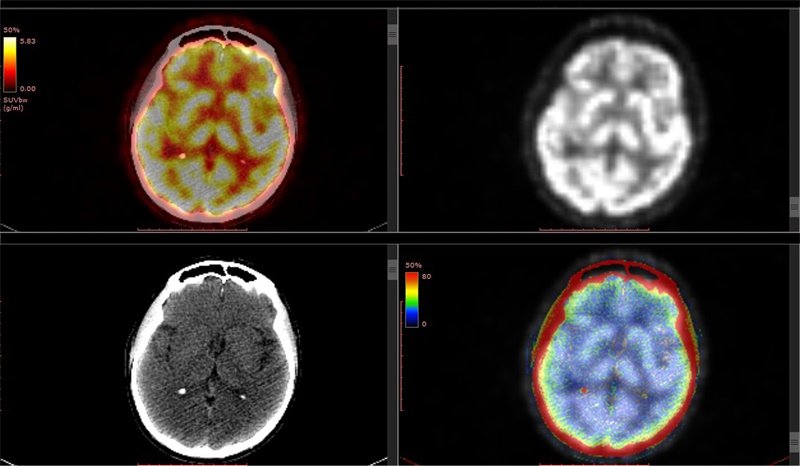

脑肿瘤包括原发性脑肿瘤和脑转移瘤,其最佳治疗手段是手术彻底切除,然因正常脑组织的不可切除性及恶性肿瘤向颅内广泛浸润性生长的特点,手术大范围彻底切除极为困难。因此,如何减少脑组织的损伤、保护脑的中枢功能、最大限度地消除肿瘤仍是现如今肿瘤学者研究的方向和奋斗的目标。